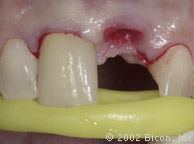

Вид после установки

Установка двух 5.0mm x 4.0mm Stealth Shouldered Abutment

Подготовка для установки временной конструкции

Установка временной конструкции